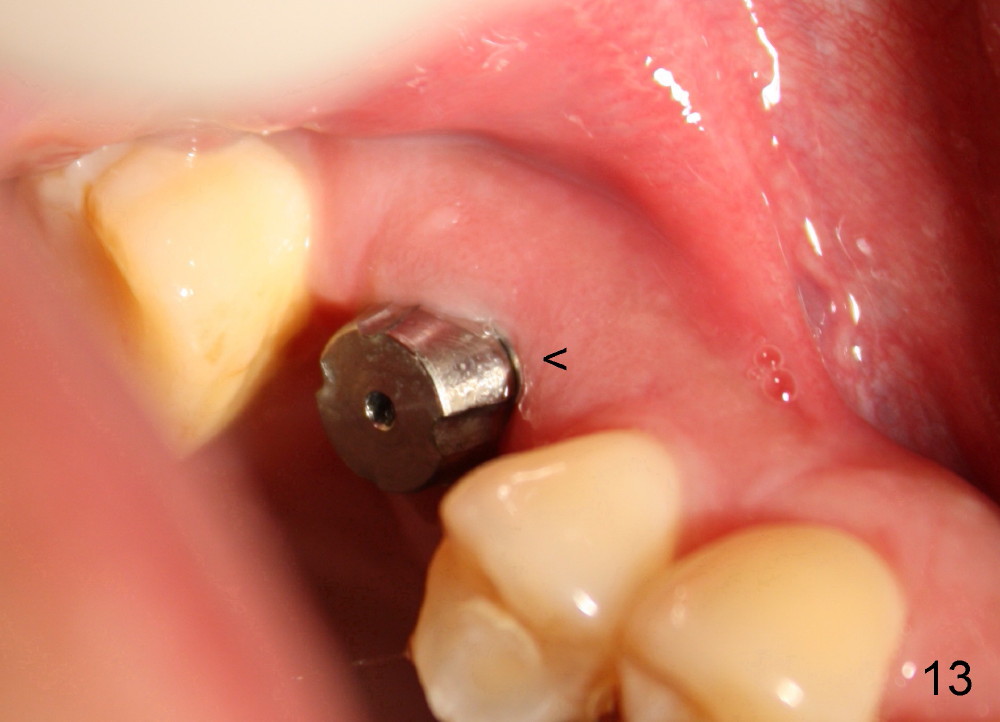

The tooth #3 has severe periodontitis with probably endodontic lesion (Fig.1,2). The patient is a 43-year-old man with apprehension of dentistry. An acute infection causes pain and tooth shift (Fig.4,5). A 7x17 mm immediate implant is planned (Fig.3). The palatal socket is shallow (Fig.6 P), corresponding to severe recessive palatal root (Fig.5 P). The osteotomy is created mainly in the buccal socket (Fig.6 B), exactly in the lingual slope of the septum. Initially osteotomes are used, followed by tap placement (Fig.7 T (4.5x20 mm at the depth of 17 mm). When the implant is placed as planned (Fig.8 I), there is more vertical contact (Fig.8 red line) than that associated with the tap (Fig.7 red line). The corresponding insertion torque is between 50 and 60 Ncm. There is only one small gap buccally, which is filled with bone graft (Fig.9 <). After the insertion of a short abutments with vertical slots (Fig.9,10 A), perio dressing is used to cover the wound. The palatal socket is expected to heal uneventfully (Fig.10 P). In fact, it does in 7 days (Fig.12 P); the bone graft in the mesiobuccal aspect is healing and stabilized (Fig.11 <). By two weeks postop, the mesiobuccal socket has healed (Fig.13 <). With removal of a diseased tooth, our body has amazing power to heal.